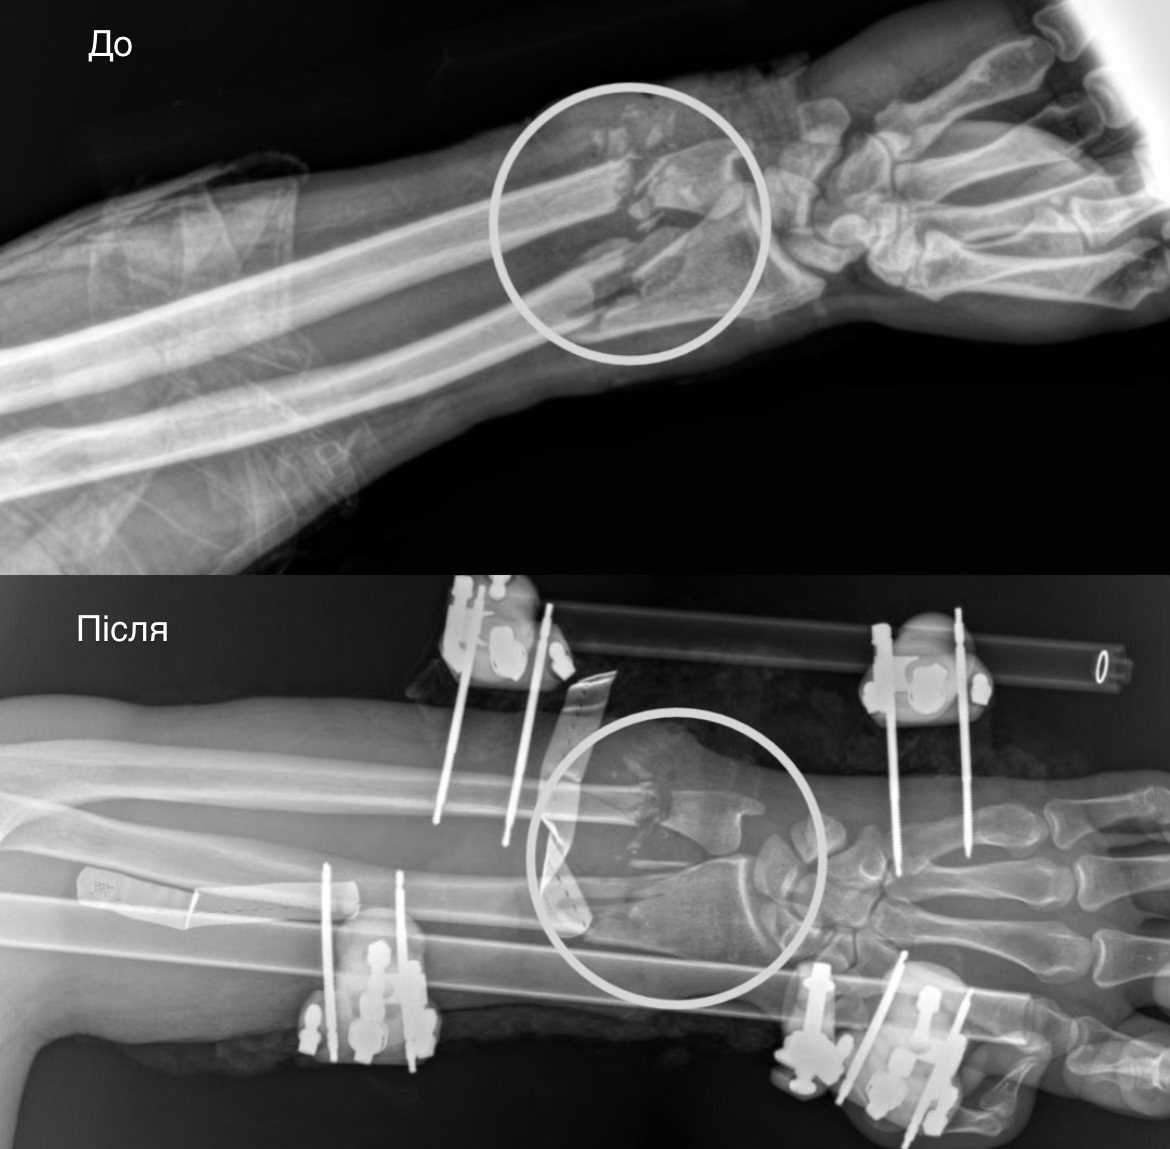

Спершу ортопеди-травматологи стабілізували переломи за допомогою апарата зовнішньої фіксації. Далі судинні хірурги відновили кровопостачання, зшивши ушкоджені судини — цей етап був вирішальним, адже без циркуляції крові тканини могли змертвіти, що призвело б до ампутації.